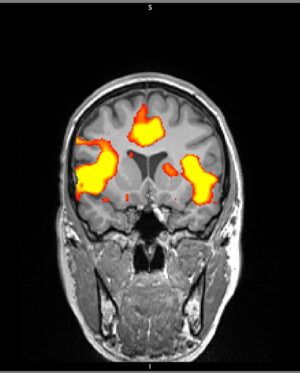

111.8K Likes – Sarah McDaniel Instagram

Caption : 🧑🏽🚀Likes : 111824

111.8K Likes – Sarah McDaniel Instagram

Caption : 🧑🏽🚀Likes : 111824